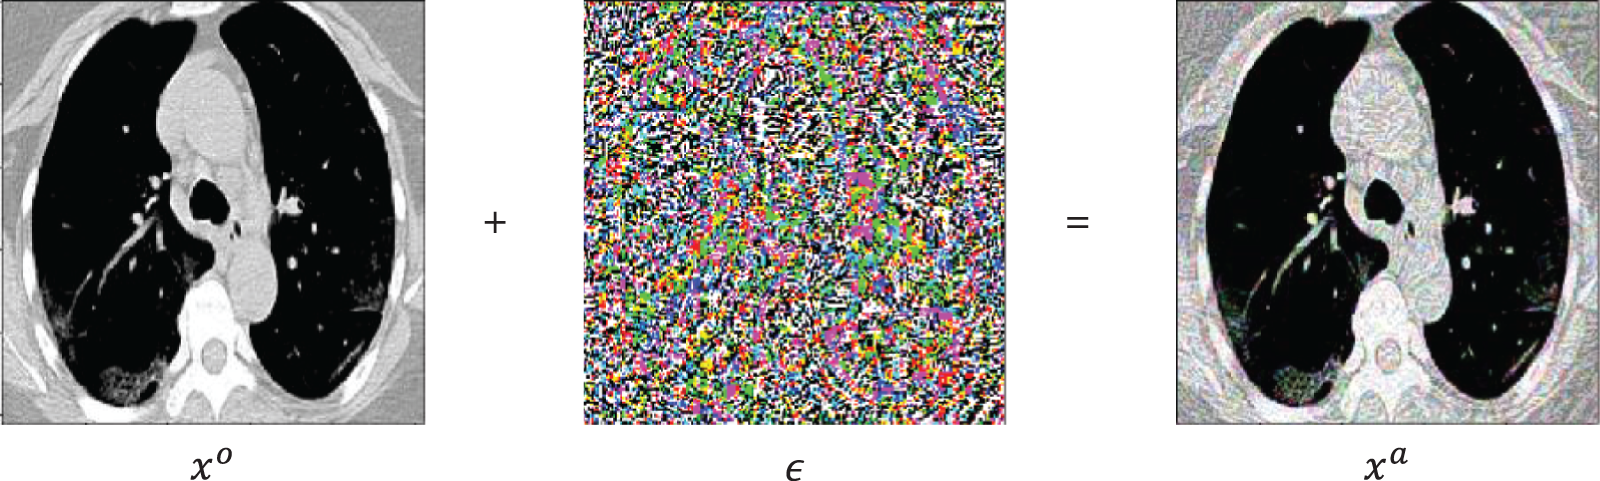

In this section, the results of the experiments are presented and discussed to evaluate the proposed system. We reported the results based on the aforementioned performance metrics. First, we presented an example from the input CT scan image through the different stages of the system, i.e., generation of perturbation and adversarial example, as presented in Fig. 7, and some of the activation maps, as presented in Fig. 8.

Figure 7: A random sample obtained from the dataset demonstrating that the addition of a perturbation

in an original image

results an adversarial image

Figure 8: Samples of the activation maps of both COVID-19 and non-COVID-19